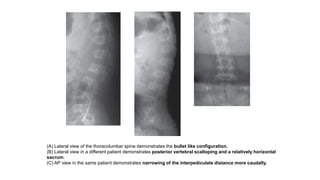

(A) Lateral view of the thoracolumbar spine demonstrates the bullet like configuration.

(B) Lateral view in a different patient demonstrates posterior vertebral scalloping and a relatively horizontal

sacrum.

(C) AP view in the same patient demonstrates narrowing of the interpediculate distance more caudally.